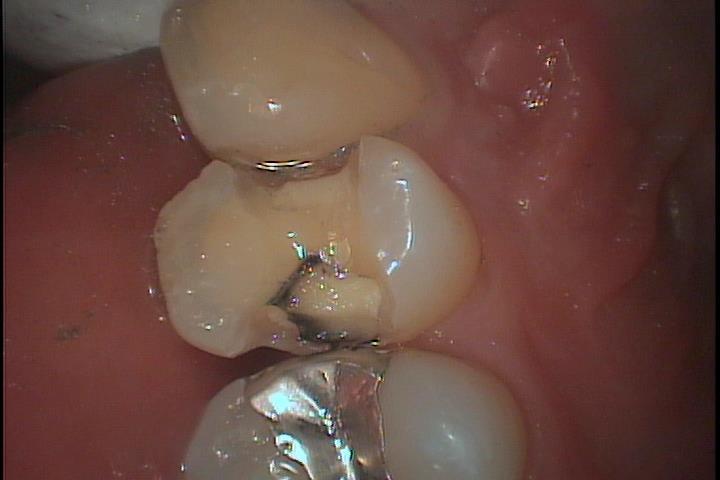

症例です

黒い部分は虫歯になっています。

神経が出てしまうと神経を取る必要が出て来ます。

メタルインレーはセメントの劣化から二次虫歯を招くことが多くセラミック修復で接着性セメントを使用してしっかり封鎖する必要があります。